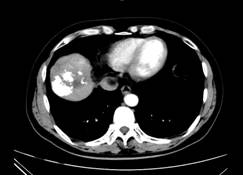

5、原发性肝癌

介入化疗栓塞术(TACE)是原发性肝癌的主要治疗方法,80%以上的患者首选介入治疗。我科在原发性肝癌的诊疗中更注重“精准”的要求:在诊断上,独立阅读影像资料,严格按国家原发性肝癌的诊疗标准执行,对不典型病例施行穿刺活检或动脉造影以明确诊断,目前,已为近20例拟诊为“原发性肝癌”的患者否定了诊断。在治疗上,术中以细导管超选择到肿瘤供血分支动脉后再行栓塞术,瘤体栓塞更彻底,周围正常肝组织损伤少,患者术后副反应轻微,3~5天即可消失;栓塞肿瘤使用液体栓塞剂,可以到达瘤体“深部”,在对肿瘤杀灭作用更强的同时,瘤体侧支血管形成的可能降低,栓塞后肿瘤稳定时间更长;在液体栓塞剂中加入无水酒精,加强对瘤体内血管网的破坏,进一步提高对肿瘤的杀灭作用。近年来,在医院“中医肿瘤多学科联合诊疗”机制下,对经介入栓塞后瘤体稳定的肝癌患者实施瘤体切除术,辅以中医药的应用,在治疗肿瘤的同时提高患者综合体质,明显提升肿瘤患者的生活质量。

病例介绍:

张××,男,56岁,外院CT增强示肝右叶“巨块型肝癌”,首次介入治疗后复查CT(2012年4月25日)所见瘤体大部栓塞,周围组织损伤小(图1a~b)。3年9个月后复查(2016年1月21日)见原瘤体明显缩小,上方肝实质复发病灶(图2a~b)。

图1a 图1b

图2a 图2b